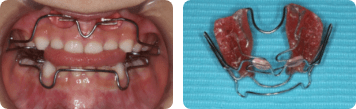

6歳臼歯の異所萌出が認められた場合、金具やゴムを使って、正しい位置に誘導します。

金具での治療

ゴムでの治療

E.O.A

装置を上下の歯で咬みこむと顎が正しい位置に誘導されます。咬む筋力が装置を介して顎に伝わり上あごを前方に、下あごを後方に押し込む力になります。自分ではずすことができ、日中や夜間に使用します。